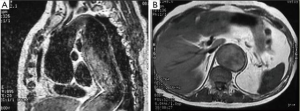

Most patients recover well and quickly from Stage I, as median sternotomy is generally well tolerated. In preparation for the procedure, CT angiography or magnetic resonance angiography for localization of the spinal artery are performed. We recommend that a CT scan of the aorta be done between Stage I and Stage II to visualize the arch repair and the elephant trunk.

Localization of the elephant trunk graft in the descending aorta is made by transesophageal echocardiography and epi-aortic ultrasound (Figure 12). After the distal aorta is clamped, left atrial to femoral bypass is instituted, adenosine is administered for cardiac standstill (16 mg) and a vertical aortotomy is done in the descending aorta at the level of the elephant trunk graft, which is then retrieved by the finger-thumb technique. After digital retrieval of the graft, the elephant trunk is clamped (Figure 13). We like to quickly place an initial clamp on the elephant trunk for hemostasis (the patient can quickly exsanguinate). However, the graft is often folded longitudinally on itself. With the initial clamp in place, we readjust and place a new clamp squarely, without any folding of the graft, above the original clamp, which is then removed. It is now important to pull down gently on the elephant trunk, as a considerable longitudinal portion of the elephant trunk graft may still be up in the aortic arch. Without “pulling down” the free upper portion of the elephant trunk, the eventual completed graft, after distal anastomosis, will be too long and thus susceptible to kinking.